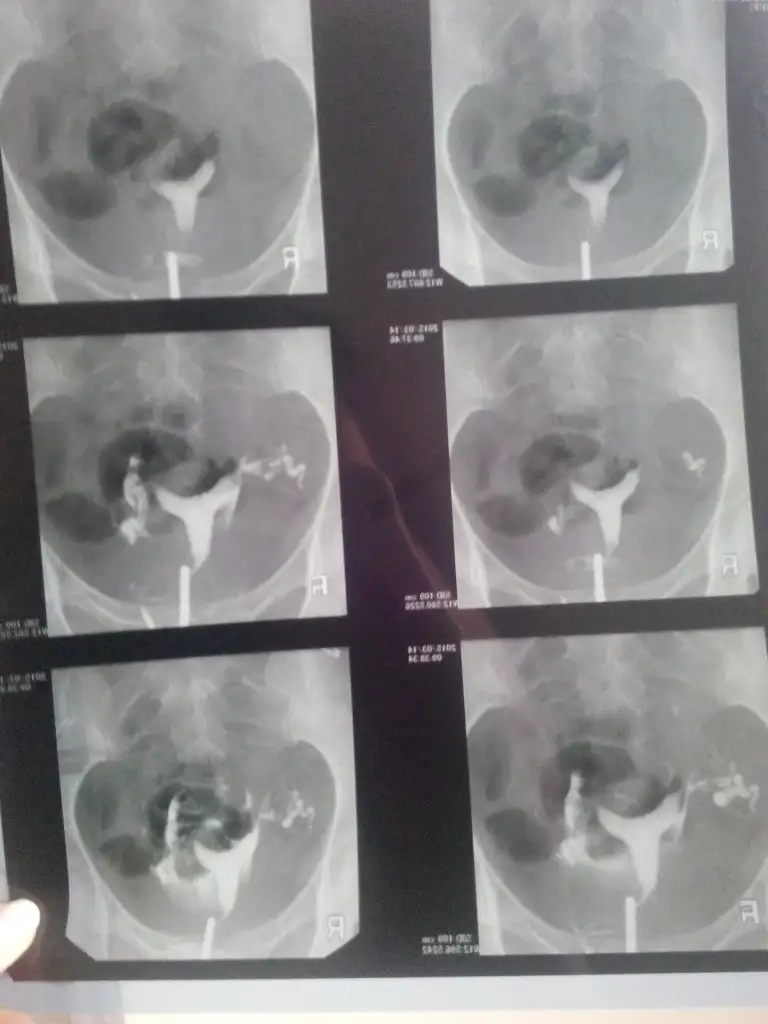

merhaba arkadaşlar cumartesi günü anestezili çektirdim iki tüpte kapalıymıs dr um 5 6 kere denemiş 5. de açılmaya başlamıs çok sükür ikiside acılduı 2 senedir boşuna üzüntü yaşamısım bilmeden rabbim herşeyin hayırlısını versin rsmini yüklicem testin birazdan bakarsınız tavsiyem drunuz cekelim derse hemen cektirin arkadaşlar

Bu kizlar filmim

Canım inşallah bebeğine kavuşursun.. Ne güzel açılmış da :nazar: Daha fazla beklemeden kavuşursun inşallah :KK68: